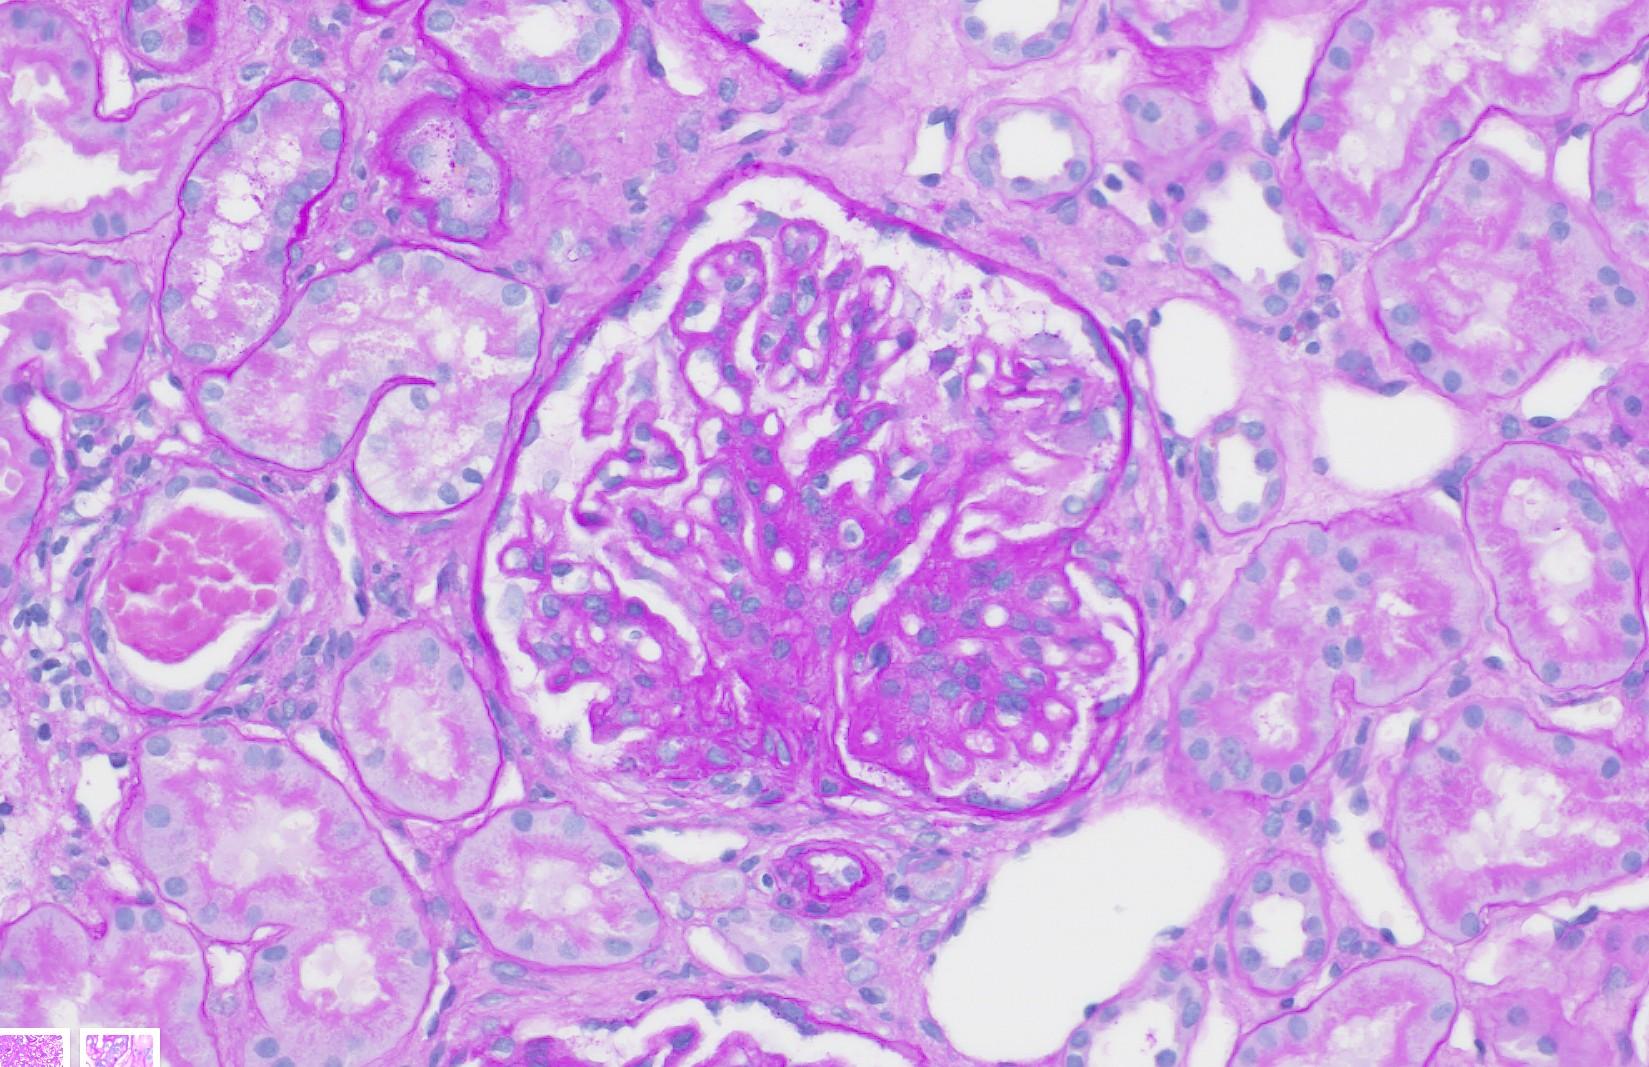

A 12-year-old boy presents with a 2-week history of periorbital and lower limb oedema. His urine dipstick shows 4+ proteinuria and his serum albumin level is low. A renal biopsy is performed. No immunoglobulin deposits were seen under immunofluorescence.

(Representative PAS-stained section)

Based on the light microscopic appearance of the renal biopsy and the clinical presentation, which of the following findings is MOST likely to be observed on electron microscopy (EM)?

A. Subepithelial "humps“

B. Extensive foot process effacement

C. Mesangial interposition

D. Subendothelial deposits with a "tram-track" appearance

E. Fibrillary material deposited in the mesangium and capillary walls

Q1 - Explained

■ Correct Answer (B): Extensive foot process effacement is the characteristic EM finding in minimal change disease (MCD), which is the most common cause of nephrotic syndrome in children and has normal or near-normal glomeruli under light microscopy.

■ Incorrect Answer (A): Subepithelial "humps" are most characteristic of post-infectious glomerulonephritis (PIGN), which often presents as nephritic syndrome, not nephrotic, and has obvious glomerular changes on light microscopy (hypercellularity). Also seen in C3 glomerulopathy.

■ Incorrect Answer (C): Mesangial interposition is typical of membranoproliferative glomerulonephritis (MPGN), which usually presents with nephritic or mixed nephritic-nephrotic features and shows changes on LM

■ Incorrect Answer (D): Subendothelial deposits with a "tram-track" appearance are also associated with MPGN, and usually has associated light microscopy findings such as mesangial hypercellularity

■ Incorrect Answer (E): Amorphous material in mesangium/capillary walls is suggestive of amyloidosis or other proteinaceous deposits, not commonly associated with the specific presentation of primary childhood nephrotic syndrome. This is a light microscopy finding, not an EM finding.